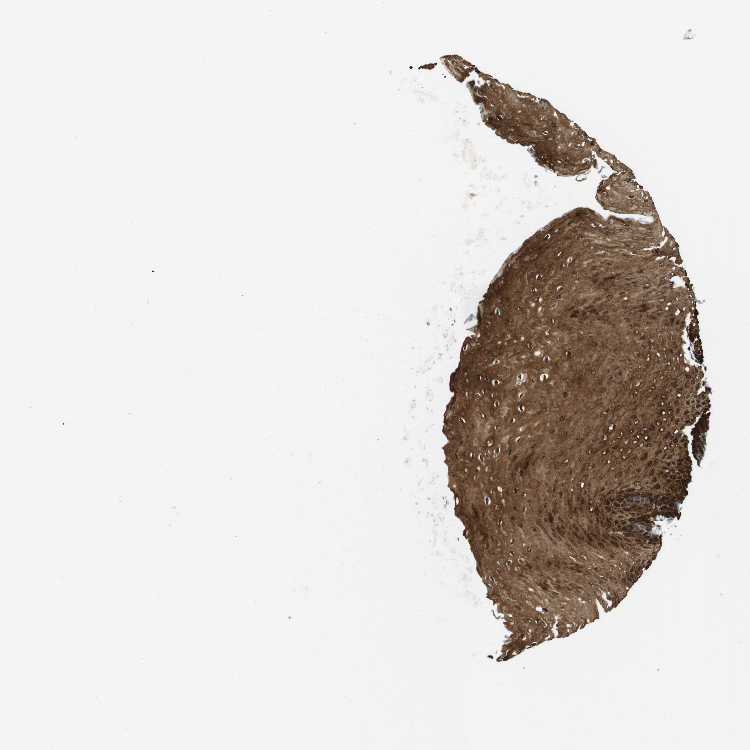

ESOPHAGUS - Antibody stainingi

Antibody staining in the annotated cell types in the current human tissue is reported as not detected, low, medium, or high, based on conventional immunohistochemistry profiling in selected tissues. This score is based on the combination of the staining intensity and fraction of stained cells.

Each image is clickable and will lead to virtual microscopy that enables deeper exploration of all samples and also displays staining intensity scores, fraction scores and subcellular localization as well as patient and tissue information for each sample.

Antibody HPA051895Antibody CAB017831Antibody CAB040577

Squamous epithelial cells HighHighHigh